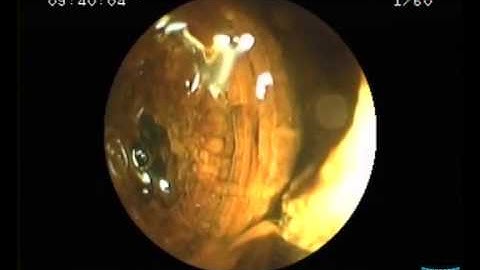

Direct Cholangioscopy